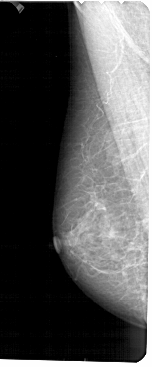

A_1489_1.LEFT_CC

LEFT_CC LINES 4951 PIXELS_PER_LINE 2191 BITS_PER_PIXEL 12 RESOLUTION 43.5 NON_OVERLAY

FILE: A_1489_1.RIGHT_CC.OVERLAY

TOTAL_ABNORMALITIES 1

ABNORMALITY 1

LESION_TYPE CALCIFICATION TYPE PLEOMORPHIC DISTRIBUTION CLUSTERED

ASSESSMENT 4

SUBTLETY 2

PATHOLOGY MALIGNANT

TOTAL_OUTLINES 1

BOUNDARY